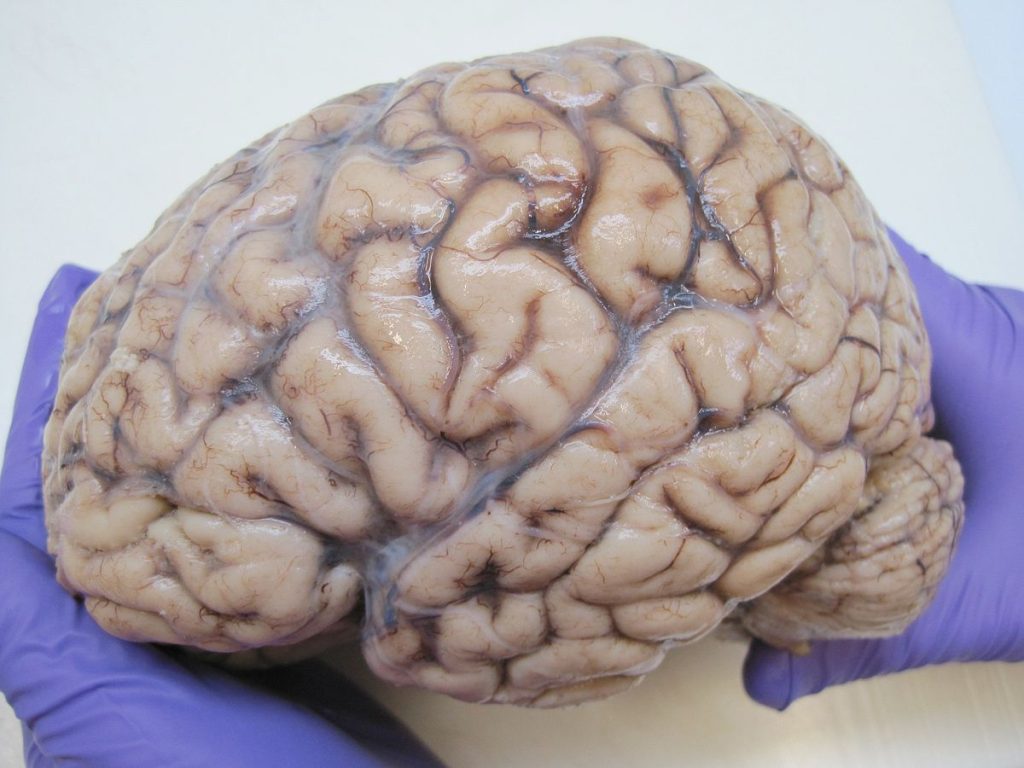

11. Your brain has a consistency similar to jello

Image source/StylecrazeAs the human brain is predominantly made of fat, it naturally is soft and squishy - just like jello. When you see a brain in a museum, it may appear to be a lot more solid than you would expect. This will likely be due to the preservation which alters it's consistency. So next time you're eating jello, just picture that's what your brain feels like!